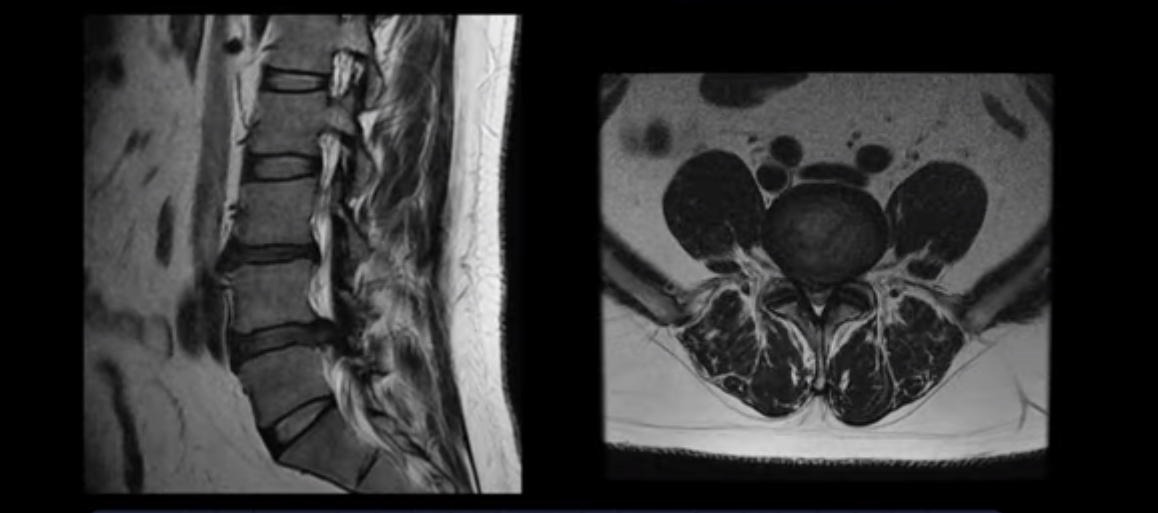

허리디스크 보존치료 좀 경험했다는 환자분들이 자기 경험으로 빗대어 방사통은 원래 오래 가는 것이 당연한 것처럼 말하는 경우가 많습니다. 그런데 저희 같은 비수술 척추치료를 전문적으로 10년 이상 수만 명씩 하고 있는 병원의 입장에서 보면 매우 답답하고 안타깝습니다. 그럼 이 4주 얘기가 파열이 심하지 않은 환자 얘기인지 궁금하실 텐데, 전혀 아닙니다. 여기 보는 MRI처럼 이 정도로 파열이 심하고, 심지어는 마비까지 있는 사람들의 이야기입니다. 이런 사람들이 최적화된 조건 하에서 평균 4주면 방사통이 가라앉는 것입니다.